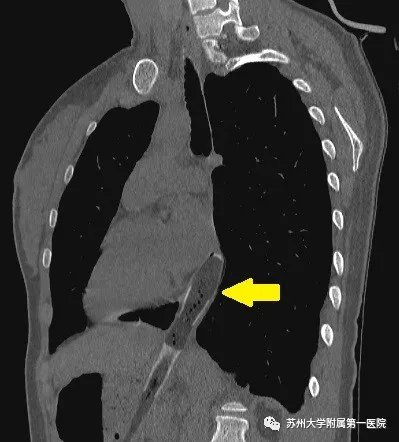

CT提示:牙刷已跨过贲门,一半在食管内,一半在胃腔内

戴医生先行胃镜探查,明确牙刷末端位于食管腔内,而刷头端位于胃腔内,整支牙刷约20cm长,横贯于贲门。一旦牙刷整体滑入胃腔,那么整个取异物过程将会变得更加困难。